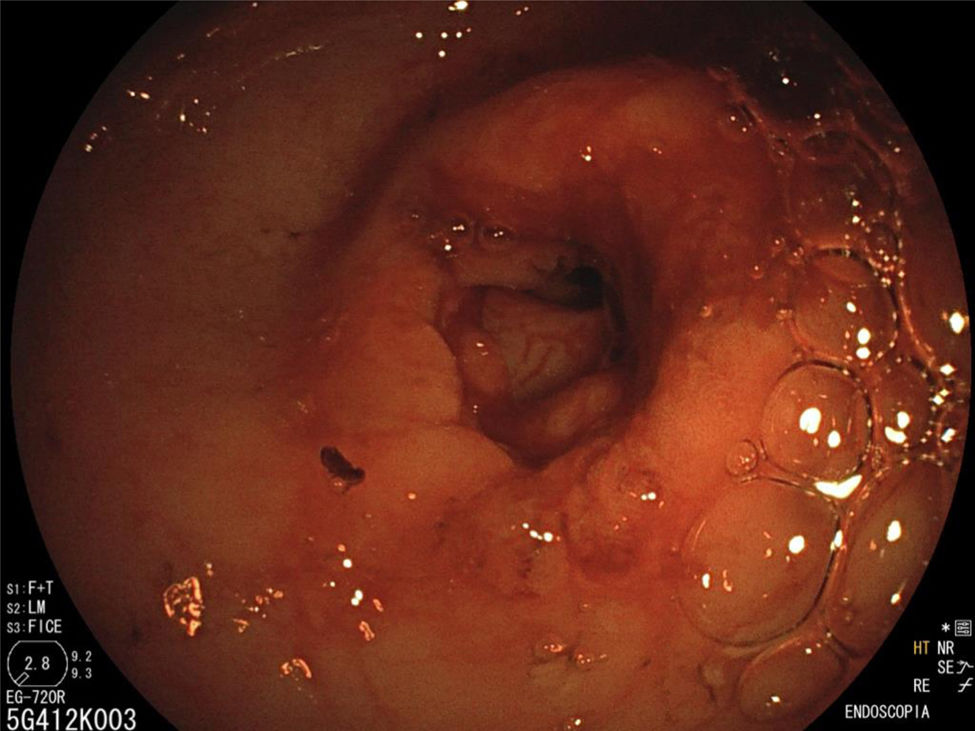

The endoscopy revealed a narrowing of the pylorus that prevented the endoscope from entering the duodenum (Fig. 1), leading to performance of hydrostatic balloon dilation (Figs. 2 and 3). The analysis of the biopsy specimens led to diagnosis of gastritis associated with Helicobacter pylori infection and foveolar hyperplasia.